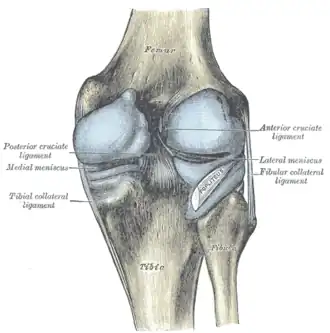

Ligaments

The ligaments surrounding the knee joint offer stability by limiting movements and, together with the menisci and several bursae, protect the articular capsule.[19]

Intracapsular

The knee is stabilized by a pair of cruciate ligaments. These ligaments are both extrasynovial, intracapsular ligaments.[20] The anterior cruciate ligament (ACL) stretches from the lateral condyle of femur to the anterior intercondylar area.[13] The ACL prevents the tibia from being pushed too far anterior relative to the femur.[13] It is often torn during twisting or bending of the knee.[21] The posterior cruciate ligament (PCL) stretches from medial condyle of femur to the posterior intercondylar area. This ligament prevents posterior displacement of the tibia relative to the femur.[13] Injury to this ligament is uncommon but can occur as a direct result of forced trauma to the ligament.

The transverse ligament stretches from the lateral meniscus to the medial meniscus. It passes in front of the menisci. It is divided into several strips in 10% of cases.[10]: 208  The two menisci are attached to each other anteriorly by the ligament.[22] The posterior (of Wrisberg) and anterior meniscofemoral ligaments (of Humphrey) stretch from the posterior horn of the lateral meniscus to the medial femoral condyle. They pass anterior and posterior to the posterior cruciate ligament respectively.[13][10]: 208  The meniscotibial ligaments (or "coronary") stretches from inferior edges of the menisci to the periphery of the tibial plateaus.

Extracapsular

The patellar ligament connects the patella to the tuberosity of the tibia. It is also occasionally called the patellar tendon because there is no definite separation between the quadriceps tendon (which surrounds the patella) and the area connecting the patella to the tibia.[23] This very strong ligament helps give the patella its mechanical leverage[24] and also functions as a cap for the condyles of the femur. Laterally and medially to the patellar ligament, the lateral and medial retinacula connect fibers from the vasti lateralis and medialis muscles to the tibia. Some fibers from the iliotibial tract radiate into the lateral retinaculum and the medial retinaculum receives some transverse fibers arising on the medial femoral epicondyle.[10]: 206

The medial collateral ligament (MCL a.k.a. "tibial") stretches from the medial epicondyle of the femur to the medial tibial condyle. It is composed of three groups of fibers, one stretching between the two bones, and two fused with the medial meniscus. The MCL is partly covered by the pes anserinus and the tendon of the semimembranosus passes under it.[10]: 206  It protects the medial side of the knee from being bent open by a stress applied to the lateral side of the knee (a valgus force).[10]: 206

The lateral collateral ligament (LCL a.k.a. "fibular") stretches from the lateral epicondyle of the femur to the head of fibula. It is separate from both the joint capsule and the lateral meniscus.[10]: 206  It protects the lateral side from an inside bending force (a varus force). The anterolateral ligament (ALL) is situated in front of the LCL.